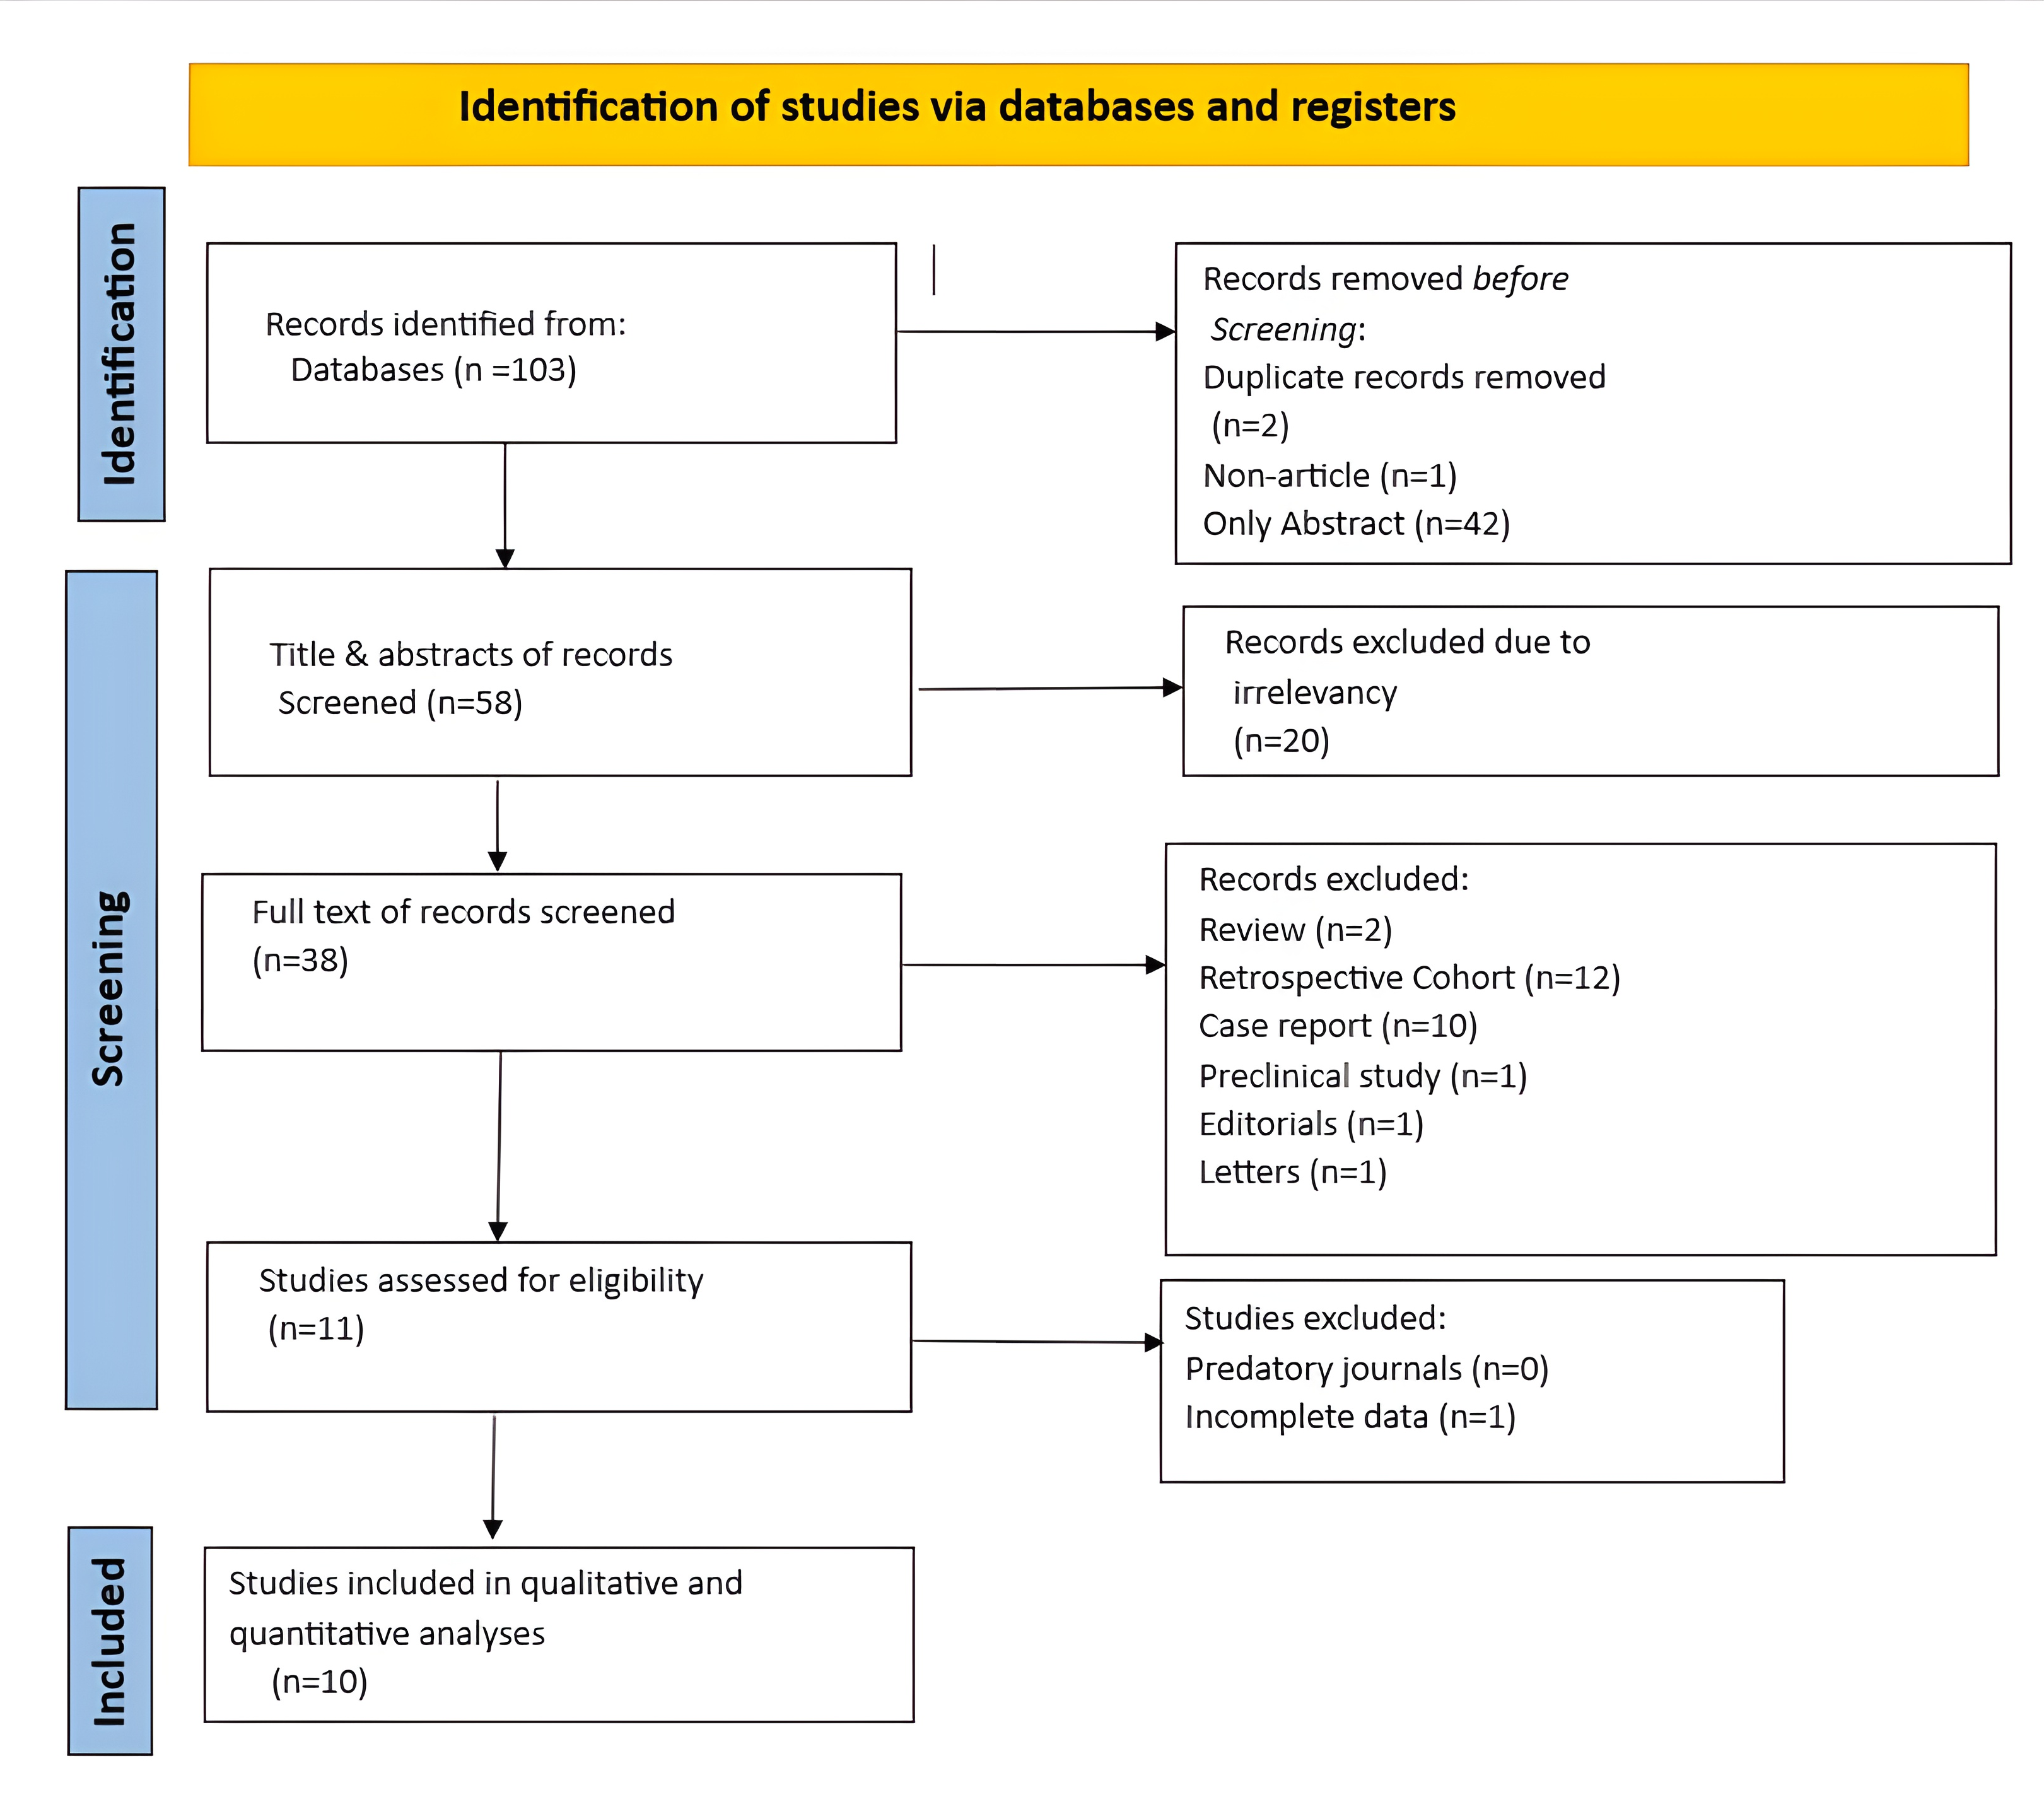

The left thyroid lobe was involved in five cases (45.5%), the right lobe in four cases (36.4%), and the isthmus in two cases (18.1%). The primary surgical approach was total thyroidectomy in seven cases (63.6%), including one patient who underwent concurrent neck dissection (Table 2). Tumor size ranged from 0.5 to 5.5 cm, with a mean size of 2.6 cm (Table 3). All the diagnoses were made post-operatively through histopathological examination (Figure 1).